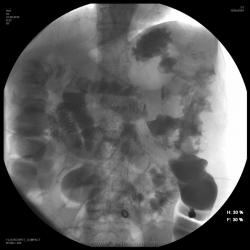

Каша конечно еще та...смею предположить рак селезеночного угла толстой кишки с образование свищей с тонкой кишкой и желудком.....

Еще, пожалуй, суб- или даже декомпенсированная кишечная непроходимость....

свищи в желудок, в тонкую кишку. гистология - аденокарцинома. в операции онкологами отказанно - "слабое сердце"... какие мнения по поводу того что изменения развились на фоне Крона?

Конечно. вероятность развития подобных осложнений на фоне Крона наиболее вероятна (как и его озлокачествление). образование таких свищей на фоне просто рака - казуистика.